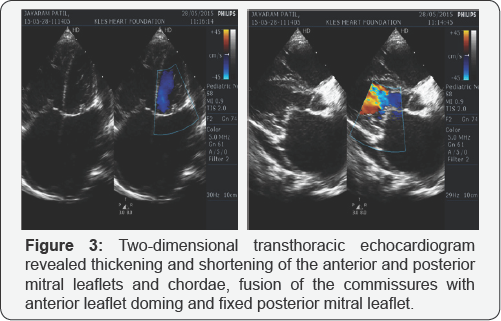

The electrocardiogram (ECG) showed sinus tachycardia with rightaxis deviation (+110°), left atrial enlargement and right ventricular hypertrophy (RVH) (Figure 1). The chest x-ray showed evidence of left atrial enlargement, pulmonary venous hypertension and pulmonary arterial hypertension (Figure 2) . The two-dimensional transthoracic echocardiogram (TTE) revealed thickening and shortening of the anterior and posterior mitral leaflets and chordae, fusion of the commissures with anterior leaflet doming and fixed posterior mitral leaflet (Figure 3) , turbulent mitral inflow jet, severe subvalvular stenosis with peak pressure gradient of 27mmHg, mean pressure gradient of 19mmHg and mitral valve opening of 0.35cm2 by planimetry (Figure 4). The patient also had severe tricuspid regurgitation with peak gradient of 76mmHg (Figure 5) and severe pulmonary hypertension, estimated right ventricular systolic pressure 91mmHg. With all these echocardiographic evidences and clinical condition of congestive cardiac failure, a diagnosis of severe MS and severe pulmonary artery hypertension (PAH) was concluded. The patient clinical condition was initially stabilized by strict bed rest and decongestive therapy with diuretics. After intial stabilization the patient was taken for commissurotomy.